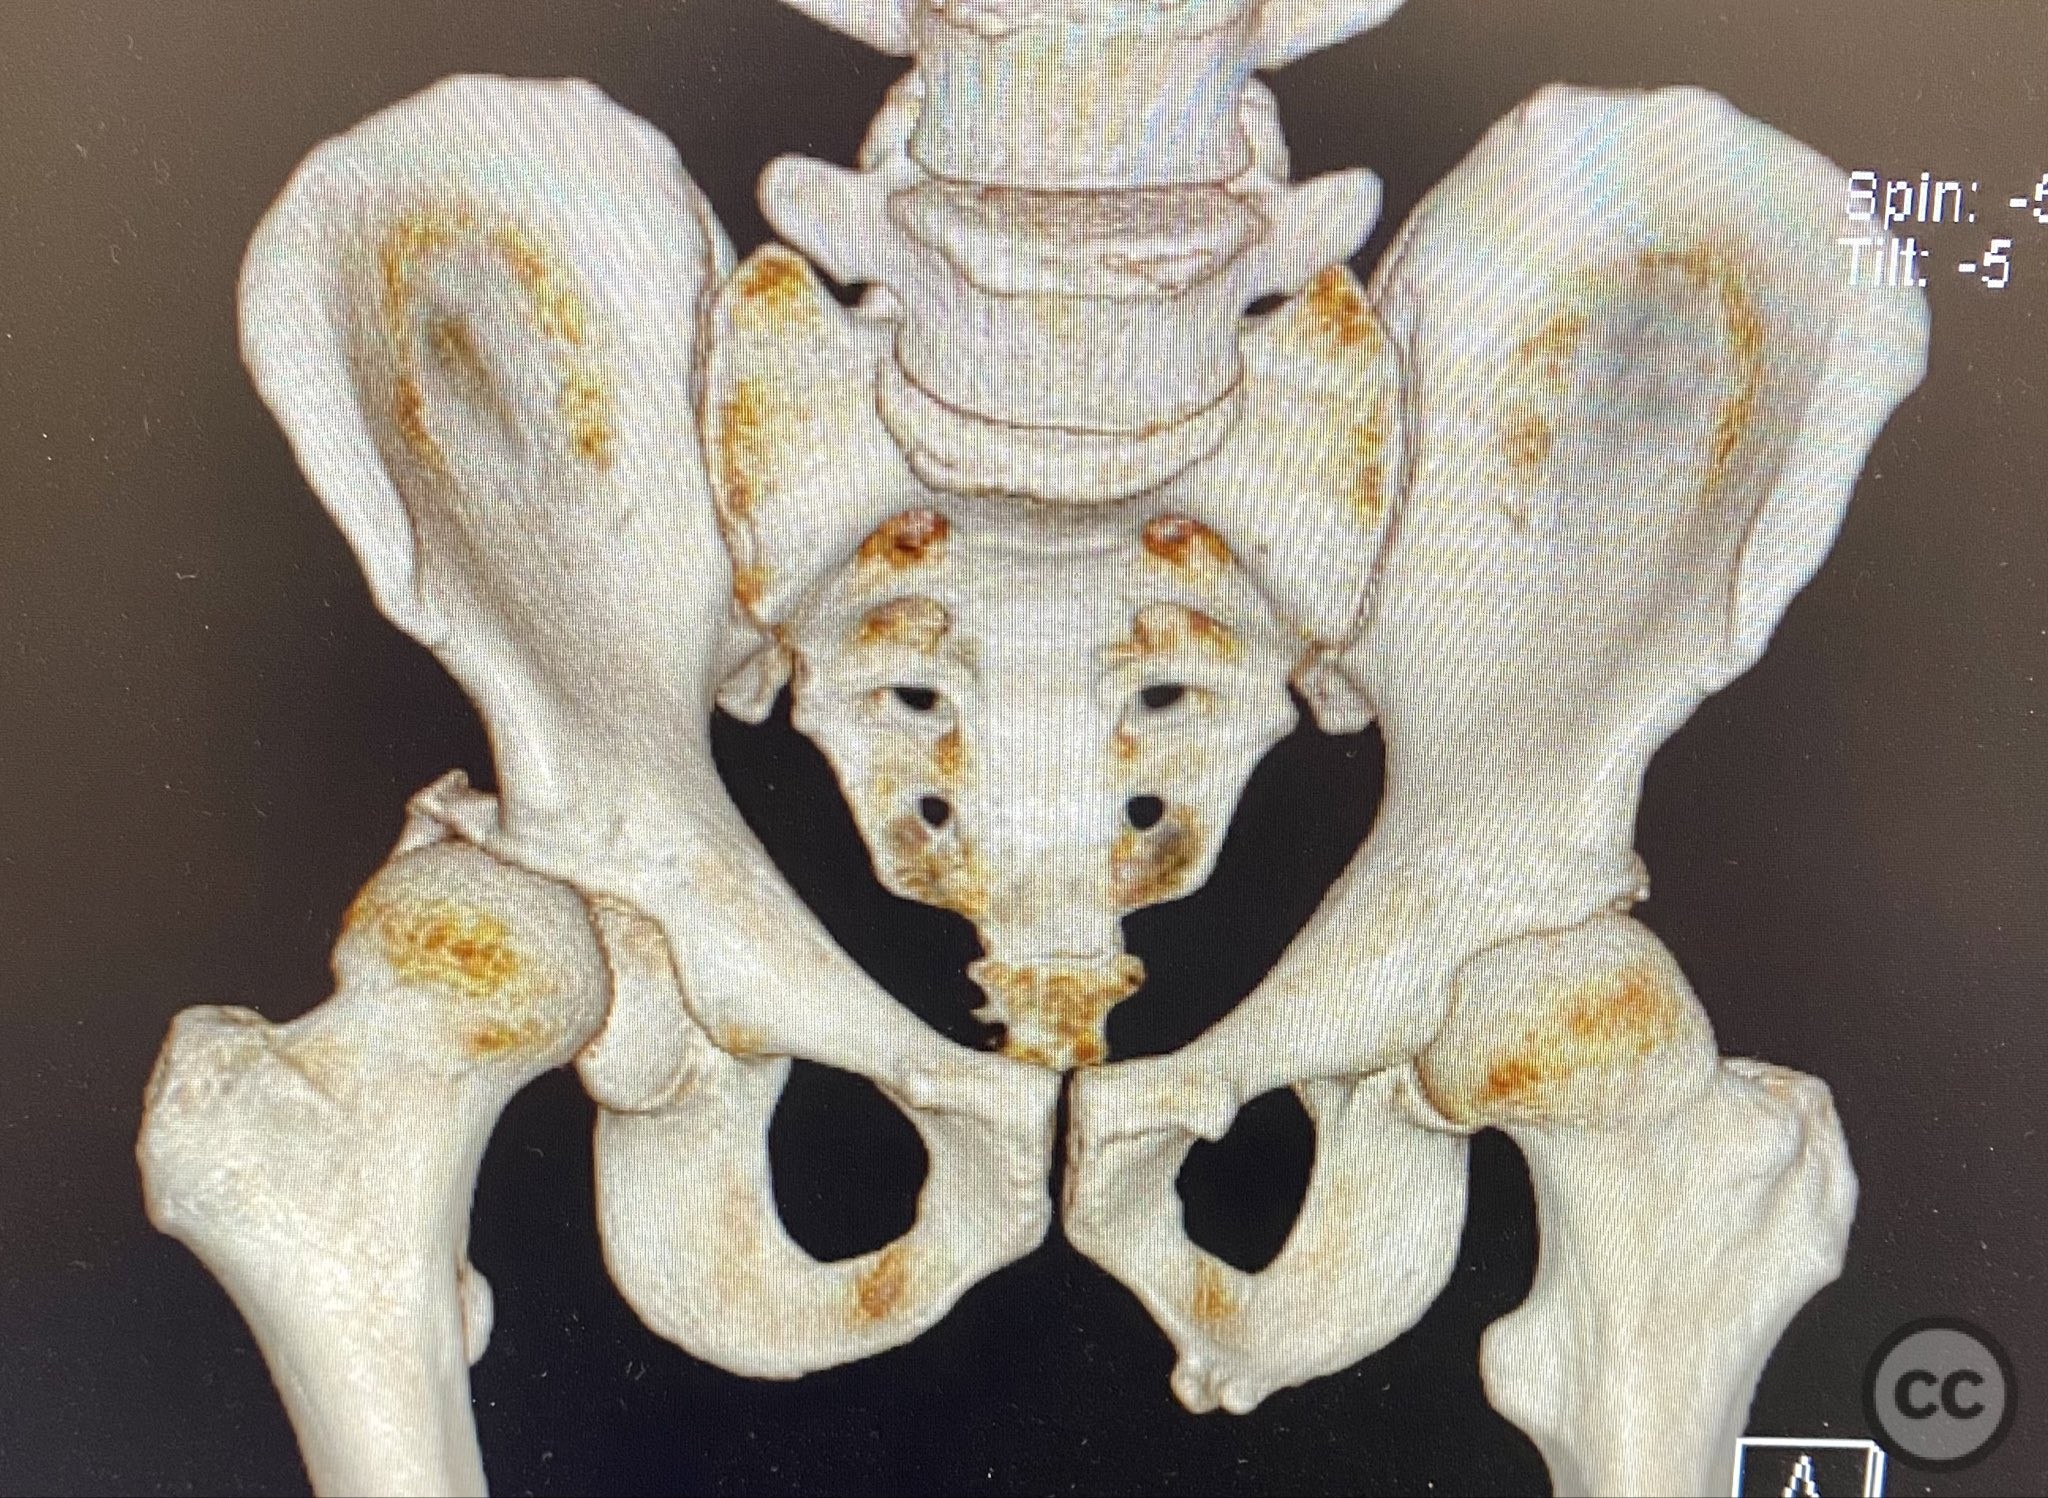

Planning remarks:  The preoperative plan included advanced imaging with CT, including 3D surface renderings, to further delineate the extent of articular impaction, wall fragment size, and comminution. The plan was for open reduction and internal fixation via a posterior Kocher-Langenbeck approach in the prone position. Elevation of impacted articular segments was planned, with structural support using autologous bone graft harvested from the greater trochanter. Fragment-specific fixation was planned with a spring hook plate for the cranial wall fragment and a reconstruction plate for the main posterior wall fragment.

The initial failed closed reduction likely resulted from interposed soft tissue or bony fragments, or inadequate sedation/muscle relaxation. Repeat reduction under improved conditions was successful prior to definitive fixation. 3D CT renderings provided enhanced visualization of impaction zones and comminution, facilitating preoperative planning for grafting and fragment-specific fixation. Intraoperatively, elevation of the impacted dome required careful manipulation to avoid further chondral injury. Use of a spring hook plate provided secure fixation of the cranial wall fragment, while the reconstruction plate supported the main wall fragment. Postoperative CT confirmed satisfactory reduction and implant positioning.